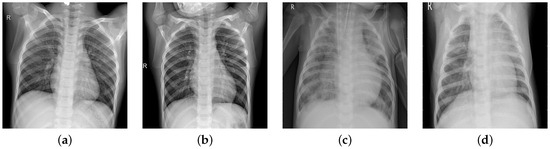

In chest radiographs radiographic features of a normal person include clear dark lung fields, well-defined lung borders, clear vascular markings, and a midline trachea. The chest radiograph of a person infected with pneumonia will exhibit localized or diffuse opacities, caused by fluid or pus-filled alveolar spaces. In Figure 1, we can observe the differences in the two types of images.

Figure 1. Normal images (a,b); pneumonia images (c,d).